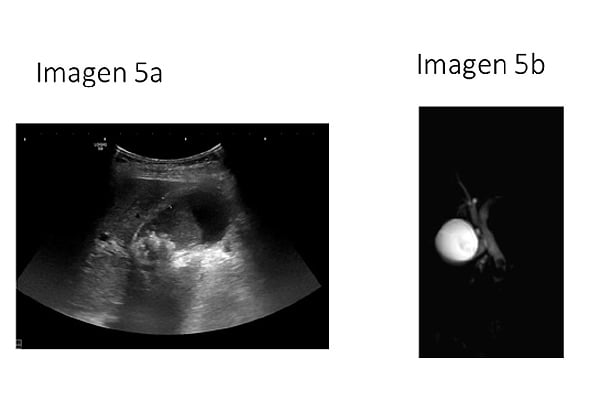

5. Varón de 58 años con antecedente de colelitiasis... ¿Cuál es la sospecha diagnóstica y tratamiento que aplicarías? (IMÁGENES 5a y 5b):

5. Varón de 58 años con antecedente de colelitiasis en una ecografía abdominal que se hizo por otra causa. Refiere dolor abdominal continuo en epigastrio - hipocondrio derecho que irradia hacia la espalda. El dolor le ha comenzado tras la ingesta y ha cedido parcialmente tras tomar un espasmolítico. Así mismo refiere que se nota un poco amarillo y que la orina es muy oscura. Constantes: Tensión arterial 140/75mmHg; Frecuencia cardiaca 100lpm; Temperatura 36,8°C. A la exploración presenta dolor a la palpación en hipocondrio derecho con signo de Murphy negativo. En la analítica de sangre: Bilirrubina total de 4 mg/dl con bilirrubina directa de 3,5 mg/dl, amilasa y lipasa normal, no tiene leucocitosis. ¿Cuál es la sospecha diagnóstica y tratamiento que aplicarías?: Usa las imágenes de ayuda (IMÁGENES 5a y 5b).